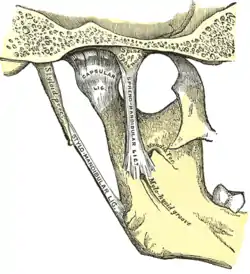

The joint seen from the inner surface. | |

The main components are the joint capsule, articular disc, mandibular condyles, articular surface of the temporal bone, temporomandibular ligament, stylomandibular ligament, sphenomandibular ligament, and lateral pterygoid muscle.

Capsule

The articular capsule (capsular ligament) is a thin, loose envelope, attached above to the circumference of the mandibular fossa and the articular tubercle immediately in front; below, to the neck of the condyle of the mandible. Its loose attachment to the neck of the mandible allows for free movement.

Ligaments

- The two minor ligaments, the stylomandibular and sphenomandibular ligaments are accessory and are not directly attached to any part of the joint.

- The stylomandibular ligament separates the infratemporal region (anterior) from the parotid region (posterior), and runs from the styloid process to the angle of the mandible; it separates the parotid and submandibular salivary glands. It also becomes taut when the mandible is protruded.

- The sphenomandibular ligament runs from the spine of the sphenoid bone to the lingula of mandible. The inferior alveolar nerve descends between the sphenomandibular ligament and the ramus of the mandible to gain access to the mandibular foramen. The sphenomandibular ligament, because of its attachment to the lingula, overlaps the opening of the foramen. It is a vestige of the embryonic lower jaw, Meckel cartilage. The ligament becomes accentuated and taut when the mandible is protruded.[5]